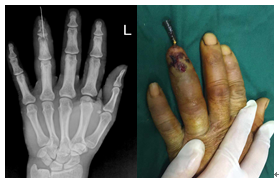

手术案例 —左手环指远节指骨骨髓炎